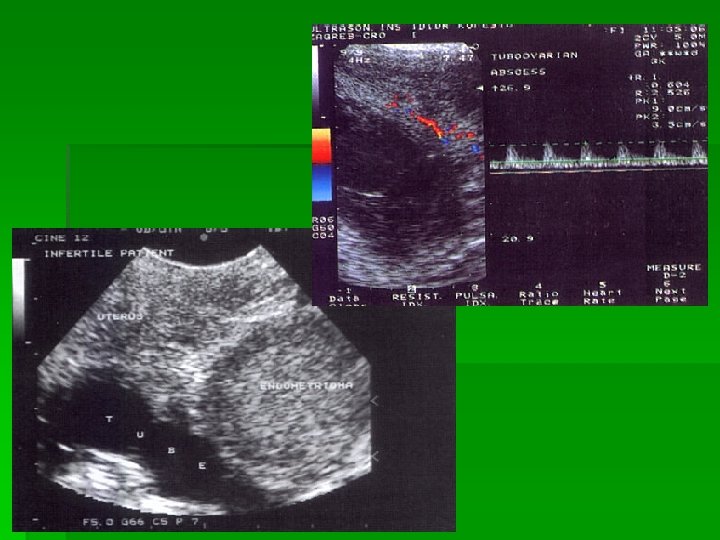

Endometriom

PID

UZV v BENIGNI tumori jajnika: v Pravilan raspored krvnih žila v Krvne žile jednakog promjera v Stijenke krvnih žila imaju mišićne niti RI 0, 42? ! v MALIGNI tumori jajnika: v Nepravilan raspored krvnih žila v Krvne žile raznolikog promjera v Prikaz tumorskih jezeraca i AV shuntova